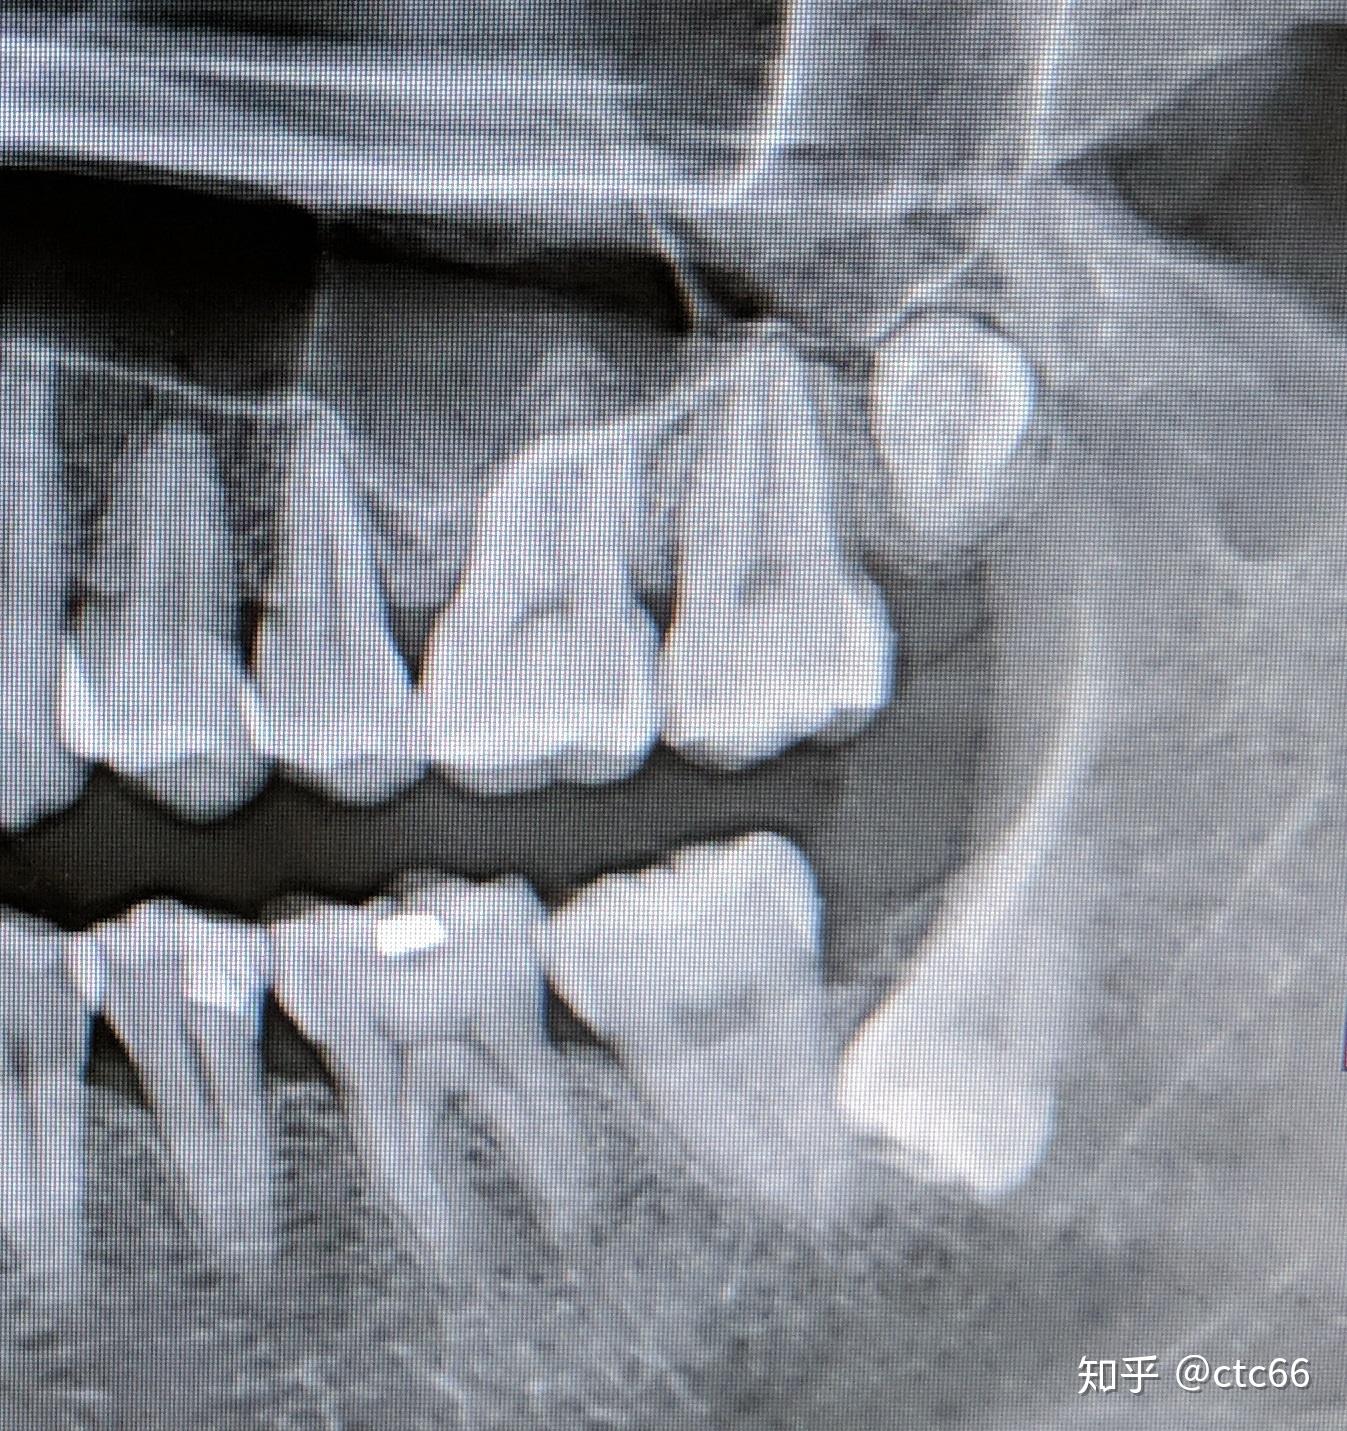

这颗上颌高位埋伏智齿能不能拔

图片尺寸1080x810